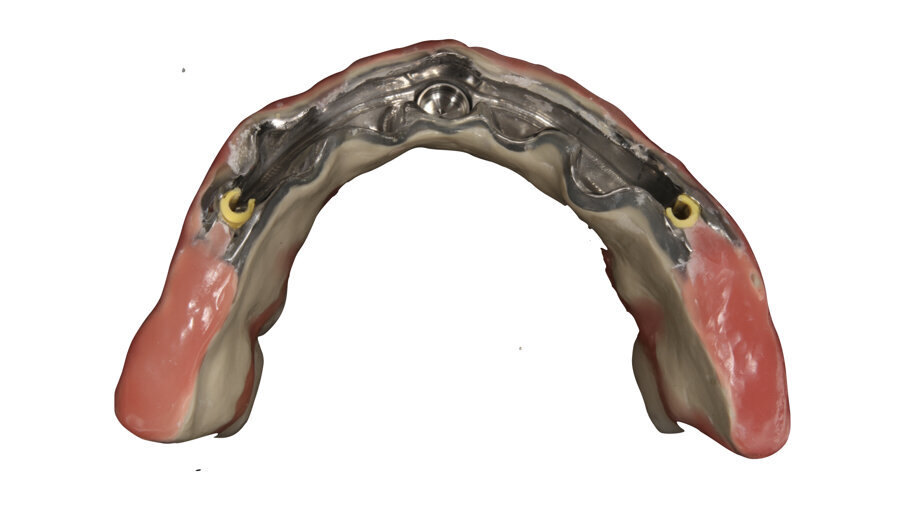

In this case, a patient presented with extremely atrophic bone in the mandible, with four short implants placed between the dental nerve foramen (Figs, 10a, 10b). After some time, patients wearing this kind of restoration with prefabricated teeth, their muscle activity increase considerably, which very often leads to fracture or debonding of the prefabricated teeth (Fig. 12). A combination of a rigid metal structure over the telescopic bar and a thimble structure made of PEEK (Fig. 13, 14) works as base for the final restorations. These were milled out of a BRILLIANT Crios disc either as single tooth units or bridges and cemented on the thimble structure (Figs. 15-17). Using BRILLIANT Crios instead of prefabricated teeth, we can increase the strength of the restoration, have good aesthetics and keep the weight low for this kind of prosthesis.

Figs. 15: Telescopic prosthesis with BRILLIANT Crios restorations. Occlusal view.

Figs. 16: Telescopic prosthesis with BRILLIANT Crios restorations. Bottom view.